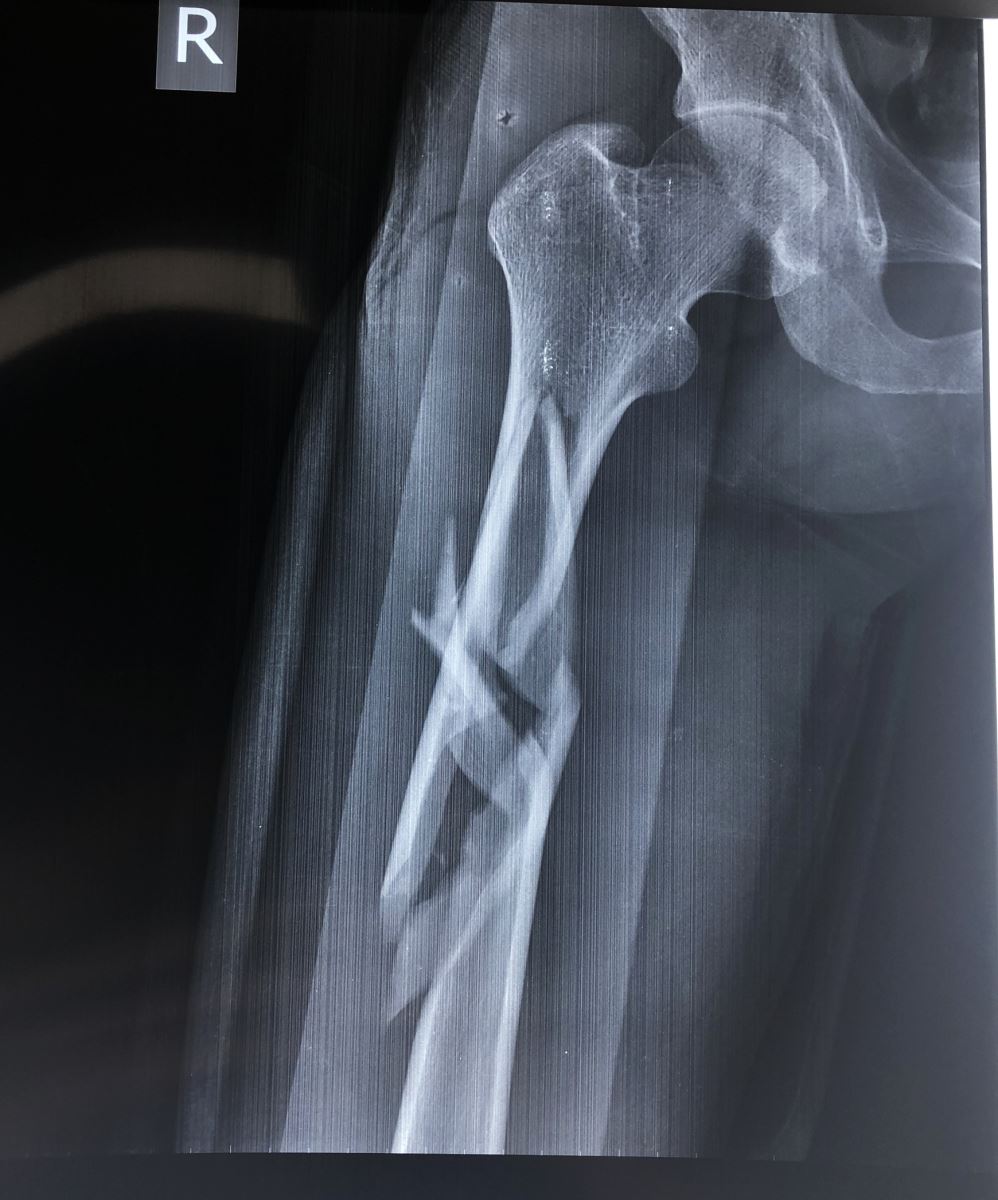

1.2. Đường gãy

Gồm có gãy ngang, gãy chéo, gãy xoắn, gãy 2 ổ hoặc gãy vụn.

- Đường gãy ngang: Thường do gập góc, dạng gãy này sau khi nắn tốt thì thường vững chắc hơn các dạng gãy khác.

- Đường gãy chéo, xoắn: Thường do gập góc kèm theo vặn xoắn cơ thể. Dạng gãy này không vững chắc sau khi nắn

1.3. Sự di lệch

Tuỳ theo vị trí gãy và có các hình thái di lệch khác nhau. Các di lệch thường gặp là gập góc, lệch sang bên, chồng lên nhau, xoay ngoài của đoạn gãy xa.

3. CHẨN ĐOÁN HÌNH ẢNH (X-QUANG)

Mặc dù chẩn đoán bằng X quang là cần thiết, nhưng cần khám kỹ lâm sàng để tránh bỏ sót thương tổn. Một số trường hợp bỏ sót trật khớp háng trong gãy thân xương đùi vì chỉ chụp giới hạn ổ gãy. Do vậy để có một phim X quang tốt cần chú ý:

- Chụp lấy được 2 khớp của đầu xương gãy ít nhất hai bình diện thẳng và nghiêng.